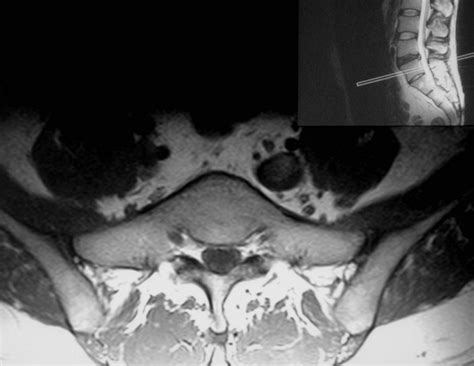

Diagnosing Lumbosacral Transitional Vertebrae

Diagnosing LSTV typically involves a combination of imaging techniques and clinical evaluation. The most common methods include:

• X-rays: Provide a basic overview of the spine and can reveal the presence of transitional vertebrae.

• CT Scans: Offer detailed images of the bone structure, helping to identify specific features of LSTV.

• MRI Scans: Provide information about the soft tissues and can help assess the impact of LSTV on the spinal cord and nerves.